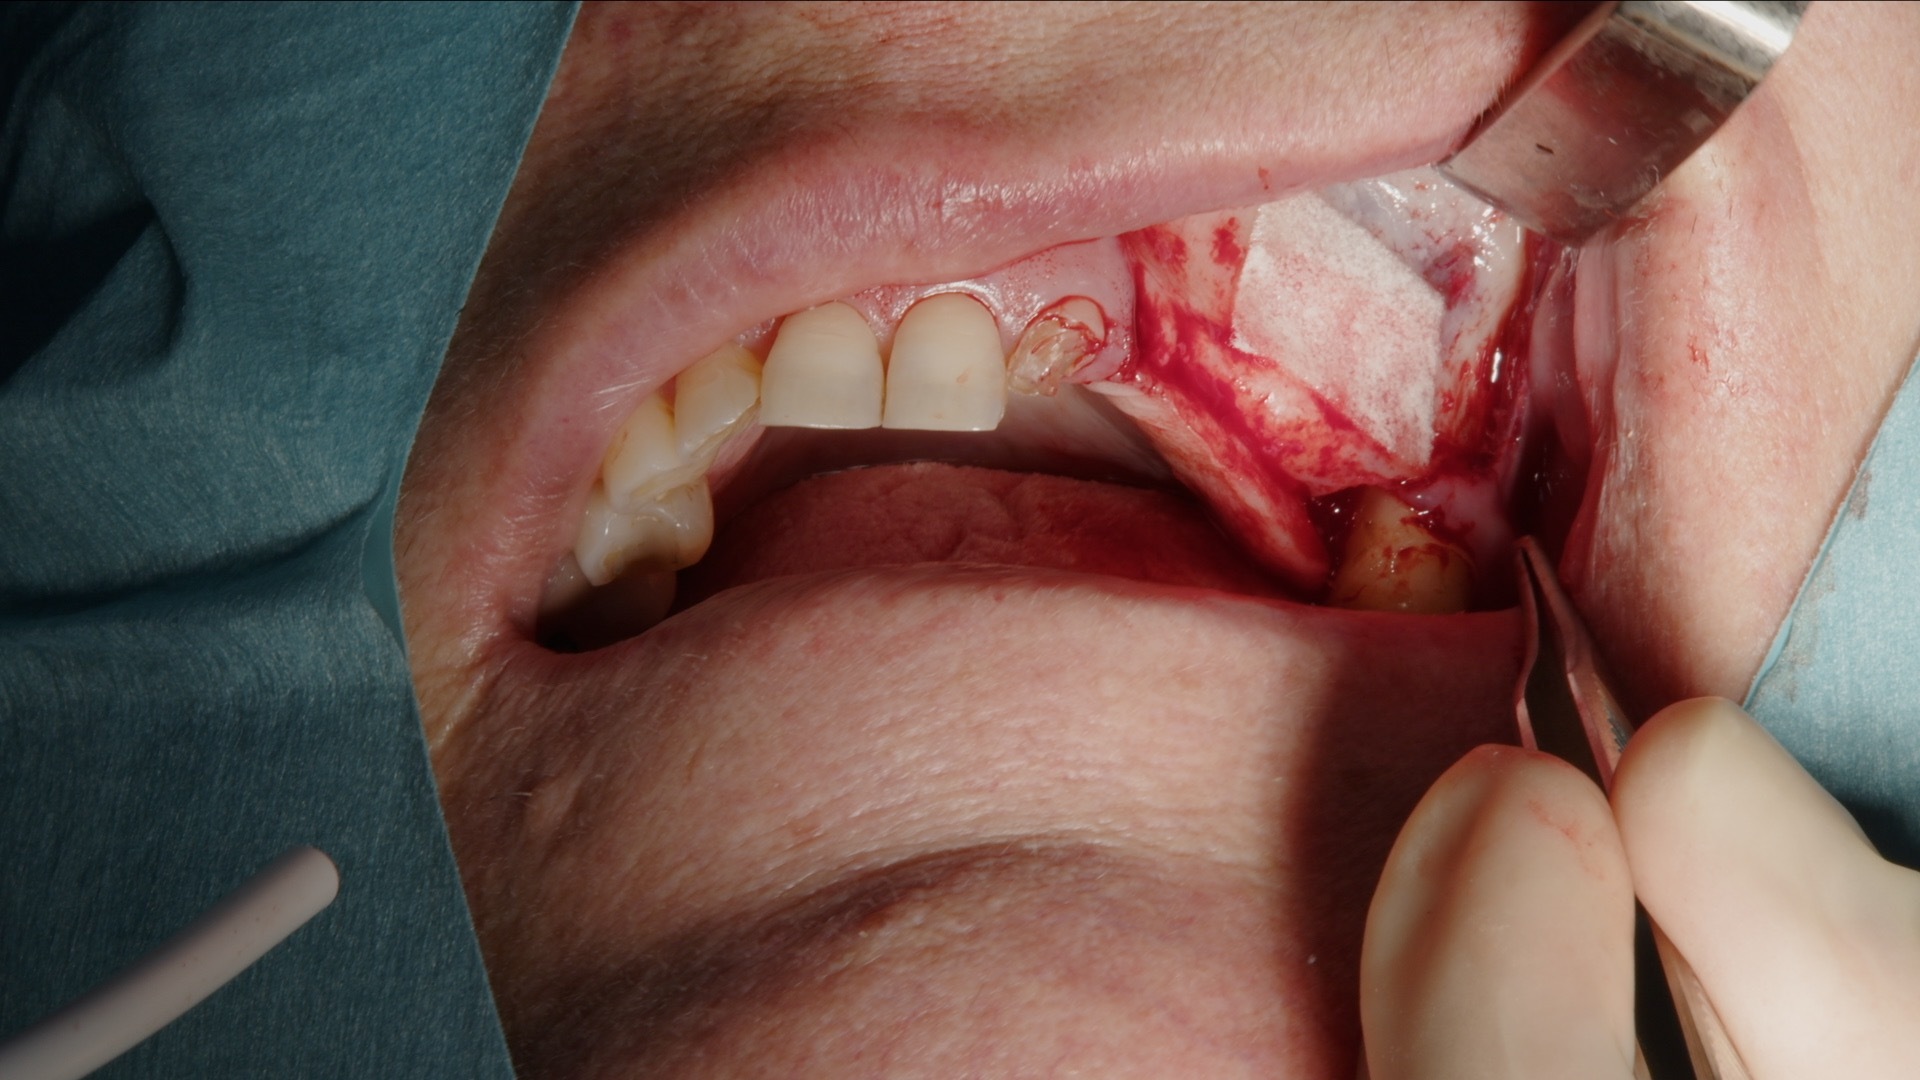

7. Dekning av lateralt vindu med Geistlich Bio-Gide membran.

Etter utfylling dekkes det laterale vinduet med Geistlich Bio-Gide kollagenmembran. Membranet fungerer som en barriere mot bløtvevsinnvekst og stabiliserer transplantatet i tilhelingsfasen. Deretter reposisjoneres lappen tensionfritt og sutureres nøye.